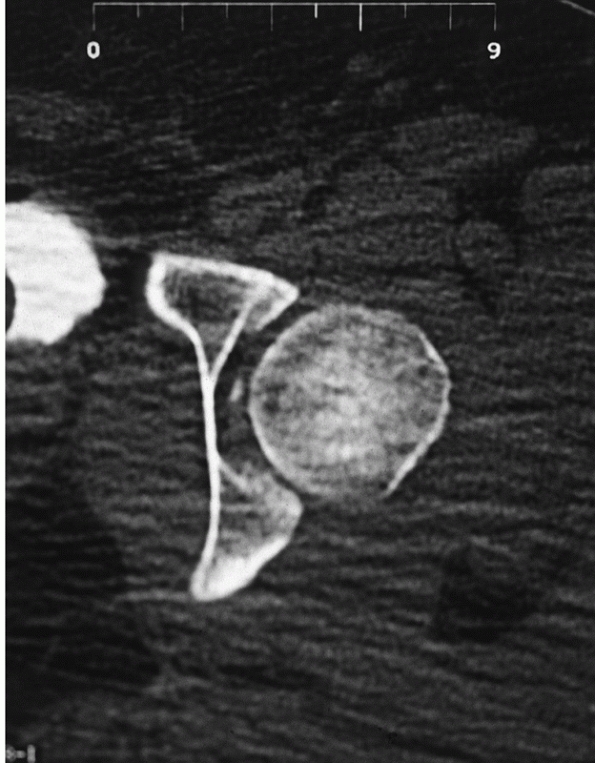

The CT scan is more sensitive in detecting small intra-articular

fragments, femoral head fractures, femoral head impaction injuries,

congruence of the hip is also easily evaluated using CT. The head

should be in the center of the subchondral ring of the acetabulum as it

becomes visible, appearing as a bullseye.173

A difference of as small as 0.5 mm in the distance from the anterior,

articular surface to the femoral head has been reported to indicate a

subluxation of the hip.18 Impaction

injuries and femoral head fractures are much more easily seen on the

postreduction CT. The quality of the reduction of femoral head

fractures is also apparent and determines treatment. The CT scan also

planning operative intervention when necessary in cases of concomitant

fracture, irreducible dislocation, or incongruent reduction. The

location, size, and number of free intra-articular fragments and the

location and size of femoral head fragments is clearly delineated,

allowing for accurate planning of operative procedures. Although CT is

very sensitive in identifying small, retained fragments, not all

intra-articular fragments will affect the treatment plan. This is

discussed in greater detail below (see “Current Treatment Options”).